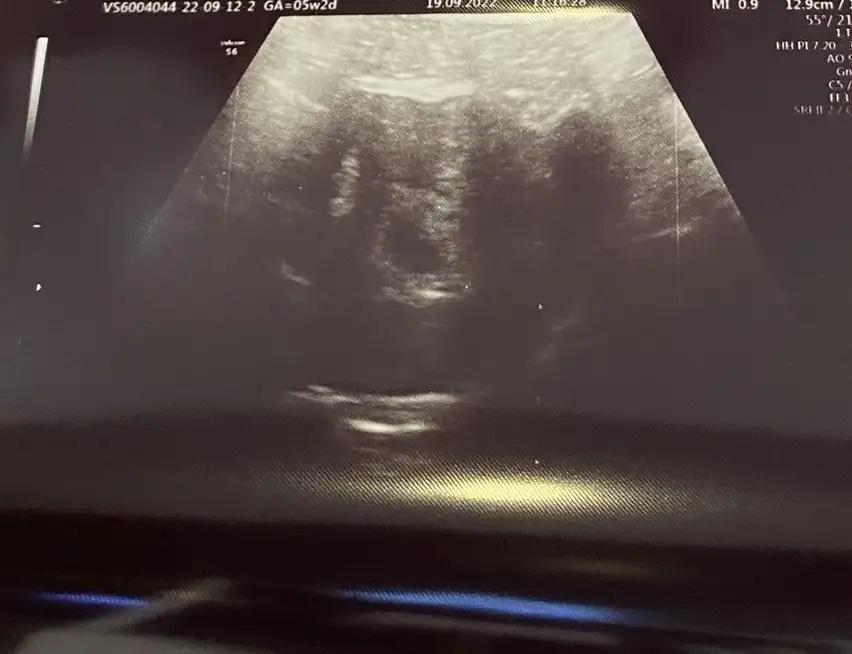

Ramziye göre bana da yorum yapar mısınız hiç anlamadım nasıl olduğunu. 5 haftalık karından çekildiOlabilir ramzide doğru cikiyo ramziyegore erkek yarın ogrenirseniZ yazın bnde yarın ogrenecem beraber yazalım bnm ramziye göre erkek sizinde erkek bakalim m doğru çıkacak mi

İnanın artık bilmiyorum bnm erkektiramziye göre kız olduğunu ogrendimRamziye göre bana da yorum yapar mısınız hiç anlamadım nasıl olduğunu. 5 haftalık karından çekildi